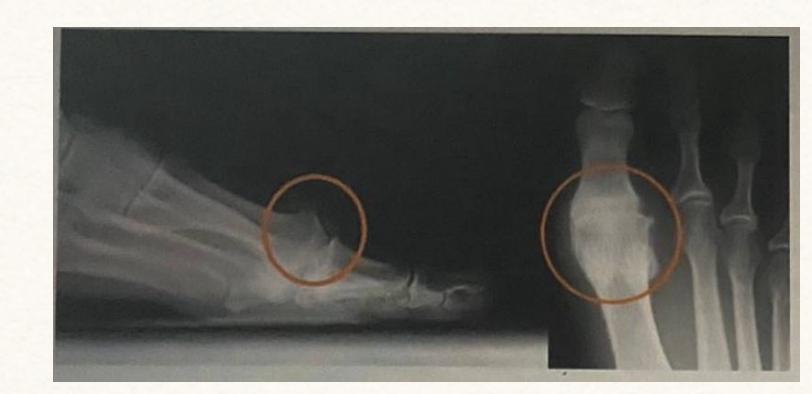

Q31 - In a foot X-ray showing possible hallux valgus, which measurement is abnormal?

- Lateral deviation of intermetatarsal angle by 14ยฐ

Q32 - In a case of painful bunion, what deformity is observed in the big toe?

- Pronation of the great toe + lateral deviation (valgus)

Q5 - A 55-year-old patient has significant foot pain. What pathology is shown on the X-ray?

- Hallux rigidus

Elderly patient foot pain diagnosis

- Diagnosis: Hallux rigidus

Question 20 - An elderly patient came with foot pain. What is the diagnosis?

Hallux Rigidus

- Arthritic condition affecting the big toe joint

- Causes stiffness and pain in the great toe

- Characterized by osteophyte formation and joint space narrowing on X-ray

Hallux Valgus (Bunion)

- Lateral deviation of the great toe

- Associated with increased intermetatarsal angle (>14ยฐ)

- Often accompanied by pronation of the great toe

Question 1: What is the deformity called in this picture?

- Answer: Hallux Valgus

Question 2: Patient complaint of severe pain and it was inflamed, what is the possible treatment?

- Answer: Surgery (Re-align 1st metatarsal, correct valgus deformity of big toe, and soft tissue balancing)